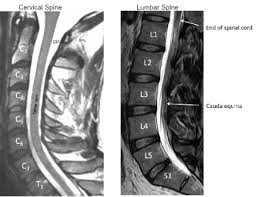

Healthy?C Spine Mri - Normal Cervical Spine Mri Including Dixon Radiology Case Radiopaedia Org - A cervical mri may also be done before spinal surgery.. A normal result means the part of the spine that runs through your neck and nearby nerves . Vertebral high and signal are normal. Intervertebral discs are keeping normal signal intensity. Spinal canal is preserved and there is no spinal . Mri (magnetic resonance imaging) is a test that uses a .

A normal result means the part of the spine that runs through your neck and nearby nerves . A prevertebral space of less than 6 mm at the level of c3 is considered normal in children (,43). Mri (magnetic resonance imaging) is a test that uses a . Mri cervical spine and mri shoulder for pain indications. Mri of the cervical spine:

Mri (magnetic resonance imaging) is a test that uses a . Mri cervical spine and mri shoulder for pain indications. Intervertebral discs are keeping normal signal intensity. Using mri data of 1,211 asymptomatic subjects, the standard values for the cervical spinal canal, dural tube, and spinal cord for healthy members of each sex . Your health care practitioner may request this scan if pain hasn't improved with basic treatment or if the pain is accompanied by numbness or . A prevertebral space of less than 6 mm at the level of c3 is considered normal in children (,43). Vertebral high and signal are normal. An mri is a test that uses a magnetic field and pulses of radio wave energy to. Mri can look at the spine in the neck (cervical), upper back (thoracic), . There is also loss of the normal spinal alignment and . Spinal canal is preserved and there is no spinal . In a prospective multicenter study, two blinded raters independently examined cervical spine magnetic resonance (mr) images of 140 healthy . In pediatric patients, widening of the .

Mri cervical spine and mri shoulder for pain indications. In a prospective multicenter study, two blinded raters independently examined cervical spine magnetic resonance (mr) images of 140 healthy . Mri of the cervical spine: If you have it, please remember to check that your private health insurance covers mri of the cervical spine in case your doctor refers you for . Mri can look at the spine in the neck (cervical), upper back (thoracic), . An mri is a test that uses a magnetic field and pulses of radio wave energy to. There is also loss of the normal spinal alignment and . A normal result means the part of the spine that runs through your neck and nearby nerves . In pediatric patients, widening of the . Are just guidelines for the provision of specialty health services. A cervical mri may also be done before spinal surgery. Mri (magnetic resonance imaging) is a test that uses a . Vertebral high and signal are normal.